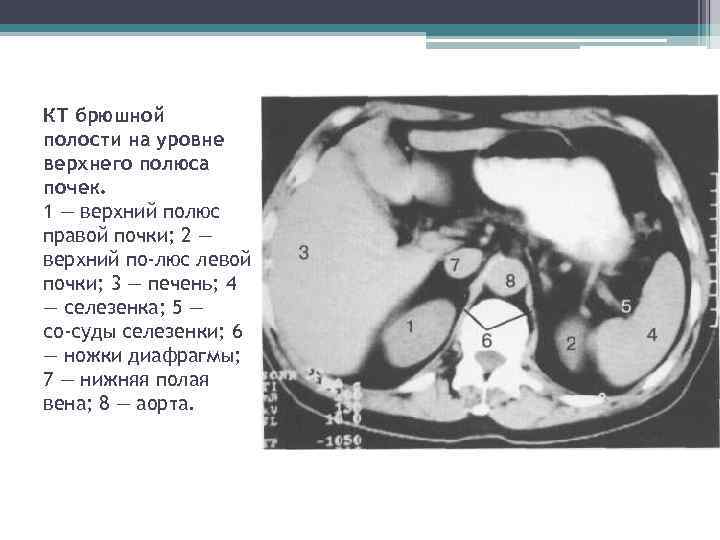

КТ брюшной полости на уровне верхнего полюса почек. 1 — верхний полюс правой почки; 2 — верхний по люс левой почки; 3 — печень; 4 — селезенка; 5 — со суды селезенки; 6 — ножки диафрагмы; 7 — нижняя полая вена; 8 — аорта.